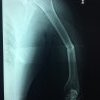

Húmero - Húmero

El Húmero (en latín, humerus) es el hueso más largo de las extremidades superiores en el ser humano. Forma parte del esqueleto apendicular superior y está ubicado en la región del brazo. ... El extremo proximal del húmero tiene la cabeza, cuellos quirúrgico y anatómico y tubérculos mayor y menor.